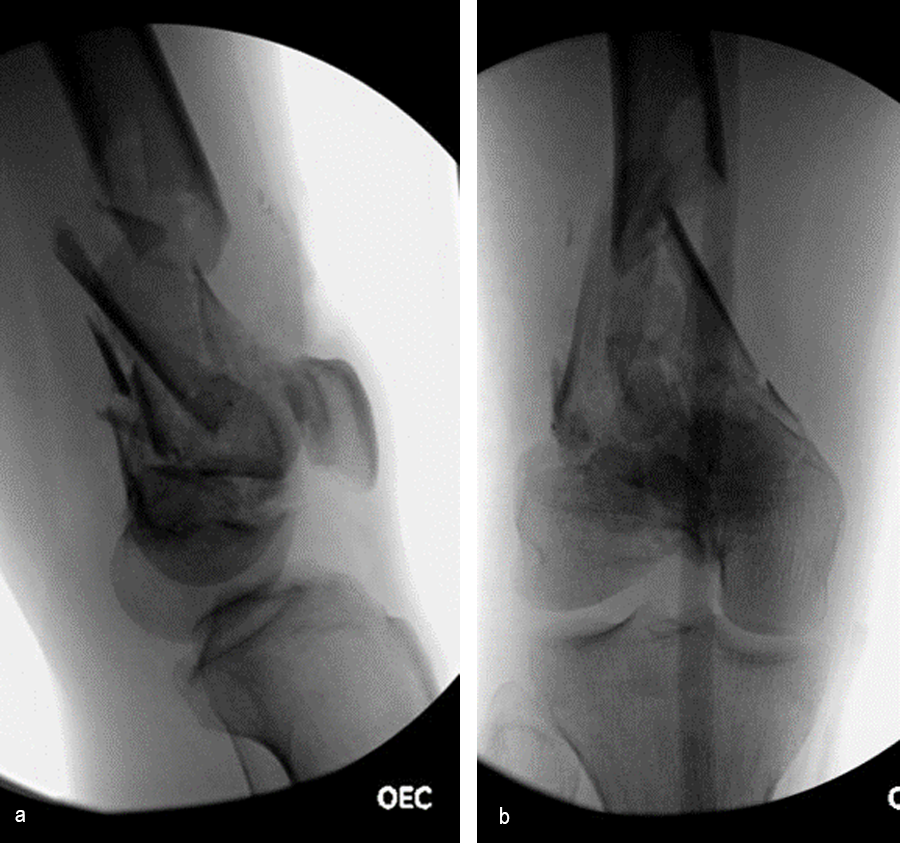

The day following admission, the patient underwent these procedures in the operating room (Fig 6):

> Washout of open injuries right side, including femur and ankle

> Open reduction of the talar injury

> Spanning external fixator of the femur and ankle

> External fixation of the left plafond/talus

At 3 days postoperative, the patient underwent a repeat washout of the right femur and right ankle. The lung injury was still recovering so no definitive fixation was performed at this time.

At 5 days post-initial surgery, the lung injury was improved, so the patient underwent open reduction and internal fixation (ORIF) of the right distal femur with resection of devitalized bone and cement spacer placement (Fig 7). Definitive fixation of the other fractures (ankle and ribs) was undertaken over time.